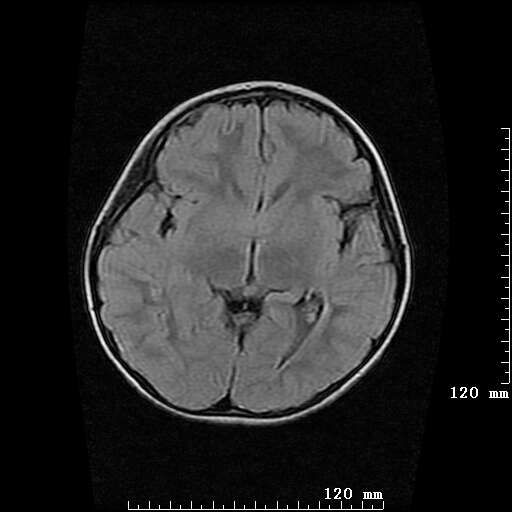

女,7岁,三岁才说话、走路。现智力尚可,走路不稳。临床怀疑大脑发育不全。

考虑 脑白质发育不良

脑折质变薄,双侧侧脑室稍扩张,支持考虑脑折质发育不良

侧脑室周围白质软化症。

考虑胼胝体发育不全,髓鞘形成不良。

支持考虑胼胝体发育不全,髓鞘形成不良。

脑裂畸形伴灰质异位

侧脑室周围白质数量减少,侧脑室不对称性扩大,左侧侧脑室后角呈方形改变,脑沟加深,结合临床考虑脑室周围白质软化症(pvl)。期待结果!

只看出灰质异位

支持脑白质发育不良。